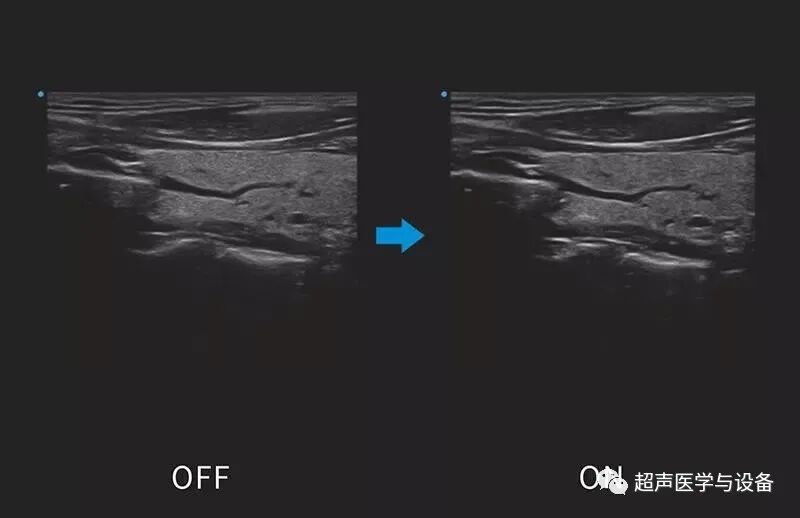

全域聚焦近些年几乎成了所有超声厂家高端彩超的标配,它打破了传统波束中场聚焦的限制,目的改善图像近中远场的图像质量,尤其是近场和远场图像信息更多,更有利于复杂疾病的诊断。SIUI的全域聚焦自动补偿信号在组织内传播过程中的非线性误差,提高成像的聚焦的精确度和一致性,实现图像声场从近到远的均匀一致。

siui彩超怎么用第84届CMEF超声厂家“群英会”---汕头超声:中国超声行业的“老大哥”_https://www.jmylbn.com_新闻资讯_第29张

siui彩超怎么用第84届CMEF超声厂家“群英会”---汕头超声:中国超声行业的“老大哥”_https://www.jmylbn.com_新闻资讯_第30张

图 / 全域聚焦